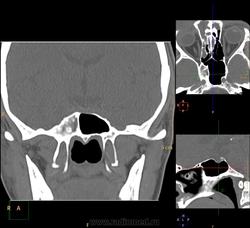

Вроде основных две, но разнообразные перегородки делят их на бОльшее количество:

Тут, например, 7 камер у одной пациентки: